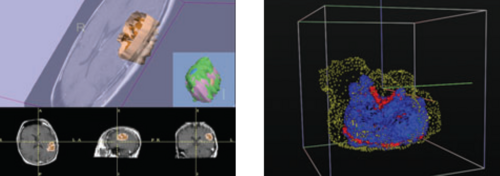

Background/Purpose: Dr. Pohl's research involves developing an automatic segmentation approach identifying major anatomical compartments from torso CT scans. Using 3D Slicer, he developed a procedure for automatically segmenting the body, bone structures, lungs, and hart from CT images (see figure). The method iterates between the identification of anatomical structures and the registration of an “atlas” to the CT data set of the subject. The atlas is based on CT data set, which we call template, and a label map that already identifies the structures of interest in the template. In the first iteration, the template with the segmentation of the body is mapped onto the CT data set of the subject. This results in a very accurate segmentation of the subject’s body. The method then combines the segmentation of the body and the CT images of the subject to identify the lungs and bone structures. In the second iteration, the method maps the atlas specific label map of body, bones, and lungs to the corresponding label map of the subject. The segmented structures are then used as a "coordinate system" used for the identification of the remaining anatomical compartments.